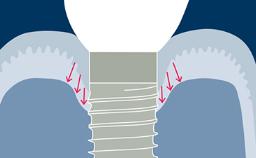

Implantes podem melhorar a qualidade de vida de um paciente. No entanto, existem vários fatores dentários do paciente que influenciam a terapia com implante e seu resultado. Eles devem ser cuidadosamente avaliados antes de iniciar o tratamento para minimizar o risco de complicações e para entender as necessidades e expectativas do paciente. Este módulo descreve os fatores odontológicos relevantes que devem ser considerados ao avaliar um paciente para terapia com implantes.